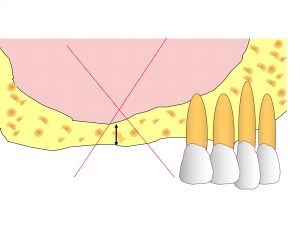

以下が初診時です。

上顎左側奥から2番目が欠損しています。

骨が吸収しているのです。

わかりやすいように骨吸収の状態を線でかいて見ます。

以下の青線が骨吸収する前の元々の骨の位置です。

現在の骨吸収した状態が以下の赤線です。

そして緑線が上顎洞の一番下の部分です。

この3つの線を組み合わせたのが以下です。

現在のように骨吸収している場合には、

インプラント治療が困難となります。

これではインプラントが長持ちするはずがありません。